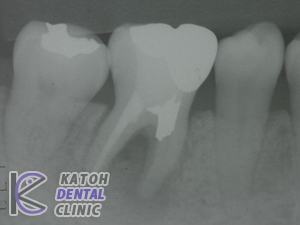

• 奥歯1本の症例

• 奥歯1本の症例2